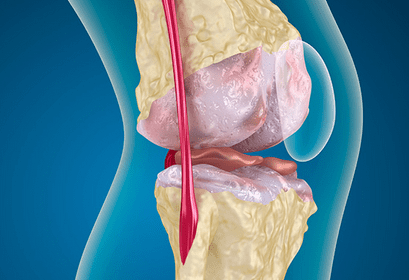

In order to move properly, your joints have a substance known as synovial fluid. This thick substance has the consistency of a gel and helps absorb shocks from normal activity such as walking, running, and turning.

A part of this synovial fluid is hyaluronic acid. When the hyaluronic acid is not produced in adequate levels, the joints are at risk for damage as the synovial fluid is less able to provide lubrication. This is particularly an issue for individuals who have osteoarthritis.

Joint viscosupplementation is the process of injecting hyaluronic acid into the knee in order to restore balance and movement in the joint.

In 1997, the FDA approved viscosupplementation as a treatment for osteoarthritis in the knee. There are multiple medications available for use in the process. While each of the medications functions differently, they were all created to allow osteoarthritis sufferers to decrease pain and increase mobility.